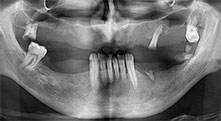

A 40-year-old patient with very poor residual dentition wanted an implant-based restoration. Because he is a smoker, a sinus lift in the maxilla with a fixed denture was contraindicated. A bar denture on four anterior implants was planned.

Piezomed B6

The alveolar ridge was split on both sides by piezo surgery (instrument: Piezomed B6). The implants were placed in the same procedure and the peri-implant bone was additionally built up using the GBR technique.

Implants

The four implants are in situ, as planned. The distal maxillary molars can still be used to fix the lined denture, which was introduced one month after implantation.